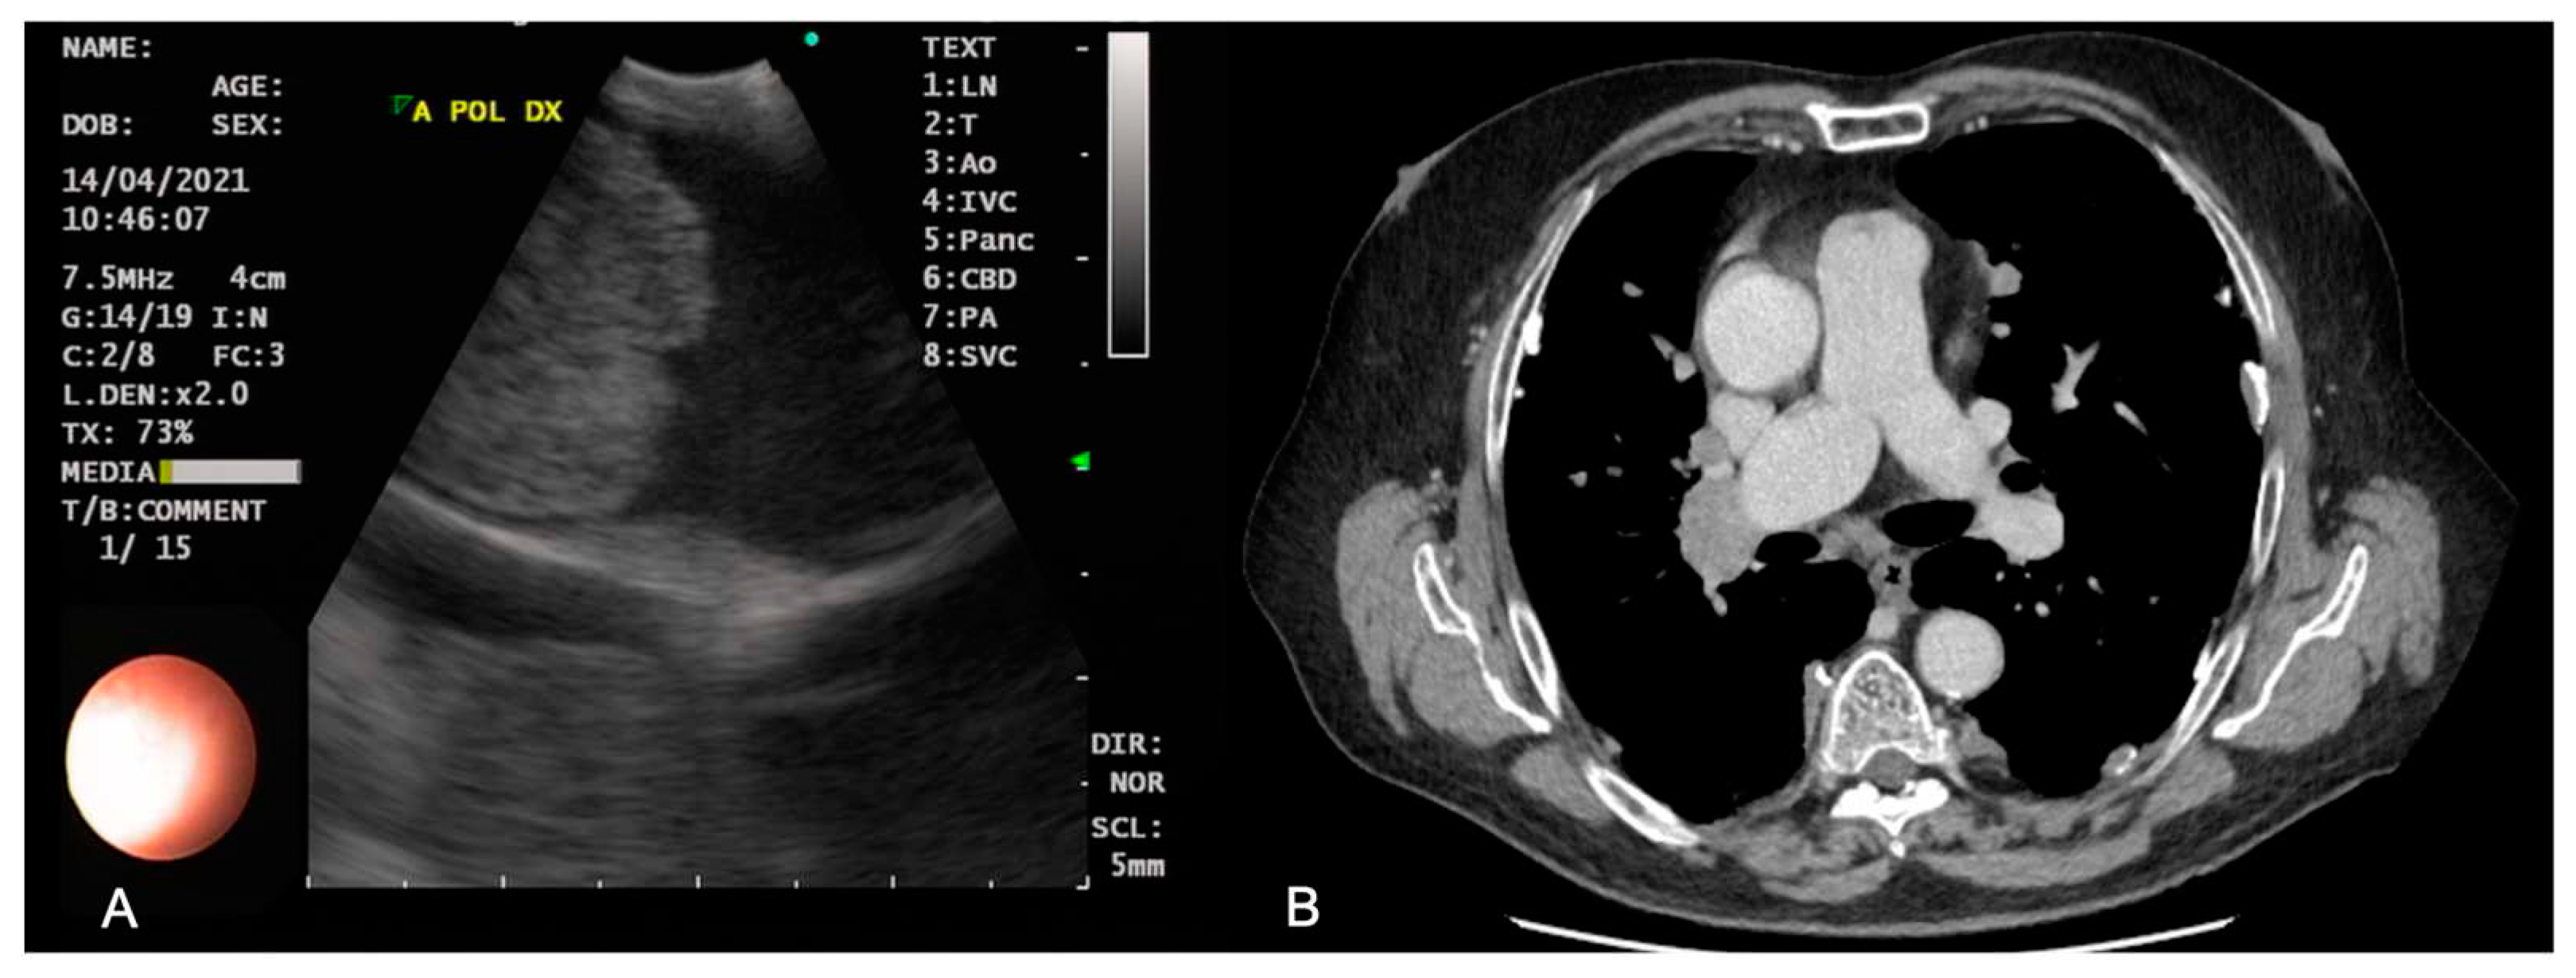

- Casoni, G.L.; Gurioli, C.; Romagnoli, M.; Poletti, V. Diagnosis of pulmonary thromboembolism with endobronchial ultrasound. Eur Respir J 2008, 32, 1416–1417. [Google Scholar] [CrossRef]

- Aumiller, J.; Herth, F.J.; Krasnik, M.; Eberhardt, R. Endobronchial ultrasound for detecting central pulmonary emboli: a pilot study. Respiration 2009, 77, 298–302. [Google Scholar] [CrossRef]

- Bertini, P.; Ribechini, A.; Guarracino, F. Improved diagnosis of pulmonary embolism causing cardiac arrest by combined endobronchial ultrasound and echocardiography. Cardiovasc Ultrasound 2020, 18, 25. [Google Scholar] [CrossRef] [PubMed]

| Pulmonary vessel assessment | Color Doppler; echocardiography | Bedside feasibility; not contraindicated in kidney failure, pregnancy and allergy to contrast medium | Poor sensibility in peripheral pulmonary embolism | [63,64,65,66] |